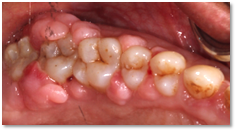

![]() | ![]() |

| Before and after surgery to reshape gums | X-ray showing results before and after bone graft surgery |